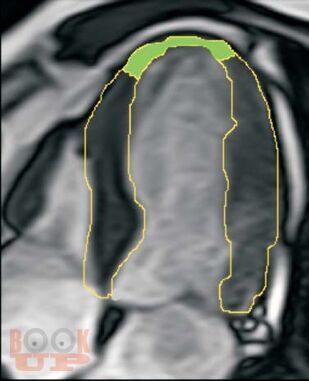

Монография представляет результаты оригинальных исследований нового диагностического метода в кардиологии – контрастированной магнитно-резонансной томографии миокарда у пациентов с ишемической болезнью сердца. Изложены патофизиологические основы методов контрастирования миокарда с помощью парамагнитных контрастных препаратов, основные методики, применяемые в клинике. Представлена визуальная семиотика ишемических повреждений миокарда, в том числе в динамике хирургического лечения – при аорто-коронарном шунтировании и аневризмэктомиях. Представлены результаты использования контрастированной МРТ при желудочковых нарушениях ритма сердца. Констатируется, что сегодня контрастированная МРТ заняла место метода выбора в оценке жизнеспособности сердечной мышцы, заменив радионуклидные исследования. Монография иллюстрирована более чем 100 рисунками и МР-томограммами.